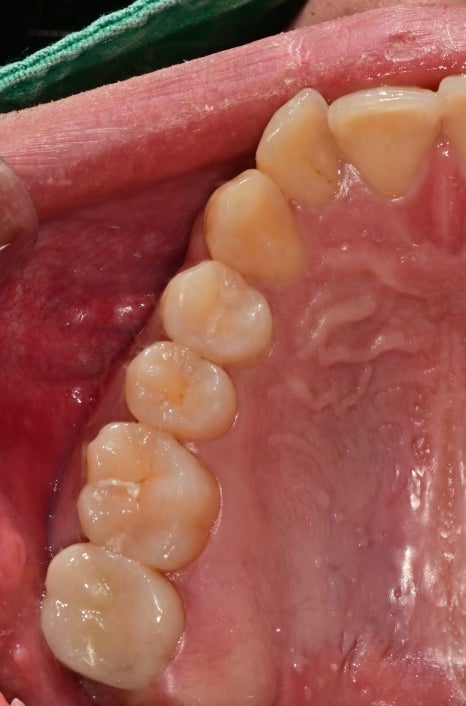

보철치료 후 교합조정

보철치료까지 완료된 사진입니다.

치료가 모두 종결된 후

초반에는 정기적으로 교합 체크를 진행했습니다.

후방부로 갈수록 치아 공간이 짧았고

교합이 긴밀하여 교합간섭을 없애고

다른 치아와 교합을 조화롭게 조정했습니다.